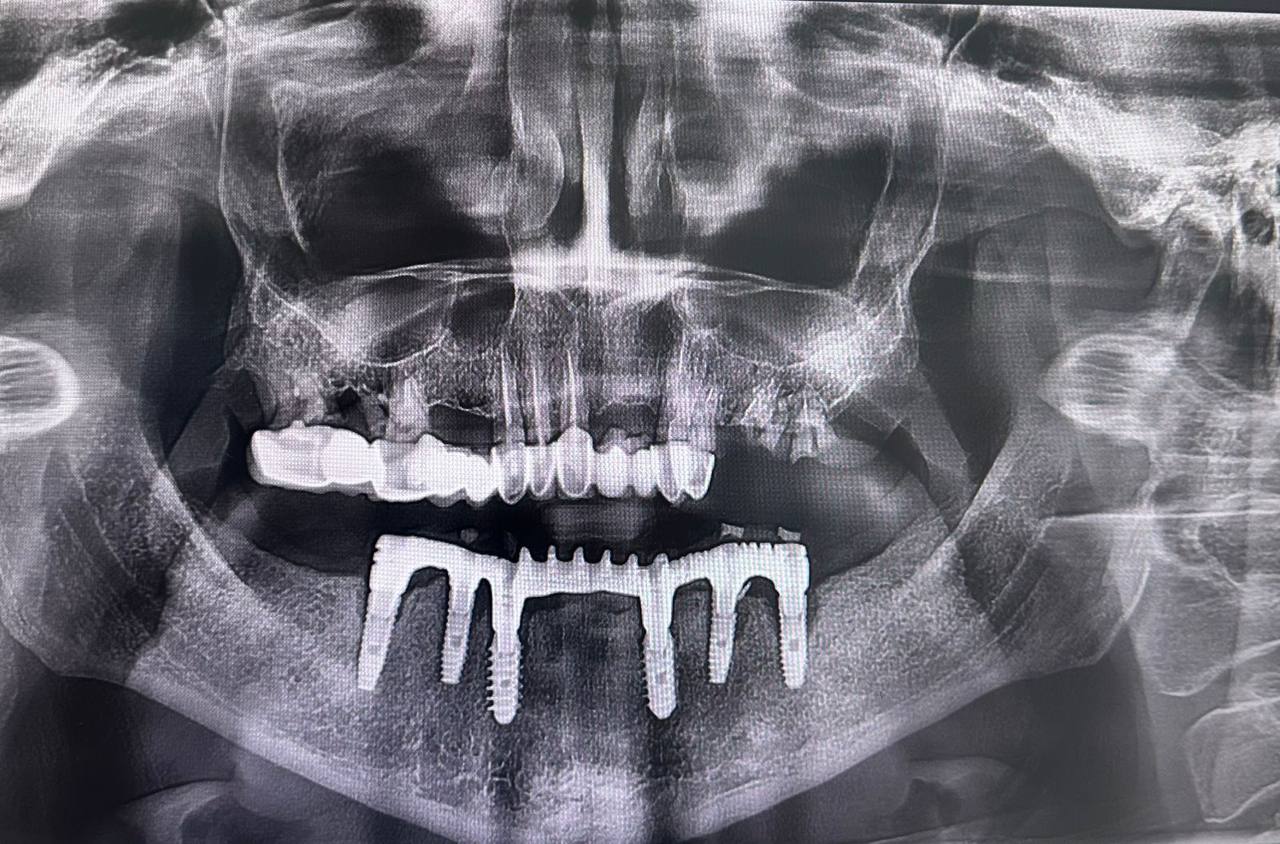

ОПТГ — это рентгенологическая диагностика, которая показывает общее состояние ротовой полости пациента. Врач получает высокоточный 2D-снимок, где видны оба зубных ряда, верхняя и нижняя челюсти, височно-нижнечелюстные суставы, гайморовы пазухи и окружающие костные структуры.

- оценка состояния костной ткани перед установкой имплантатов и т.д.

КТ — это более детальное исследование зубочелюстной системы человека. Специалист получает возможность изучить зубы, костные и мягкие ткани на 3D-изображениях. Компьютерную томографию обычно назначают в особо сложных клинических ситуациях, чтобы подобрать эффективное лечение.